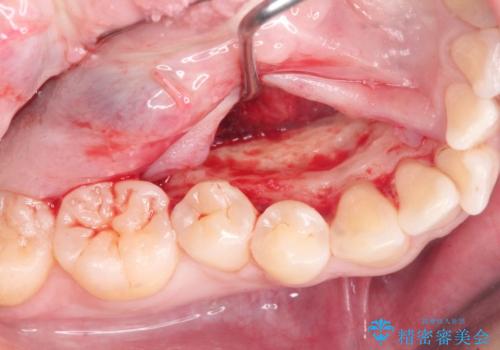

矯正の後戻りを防ぐ骨隆起の切除

- 矯正治療に先立ち、舌の収まりを改善し矯正治療後の後戻りリスクを下げるため、大きな下顎隆起の切除を計画します。

このあと、両側の隆起を除去し、舌の収まりが楽になったと喜んでいただくことができました。